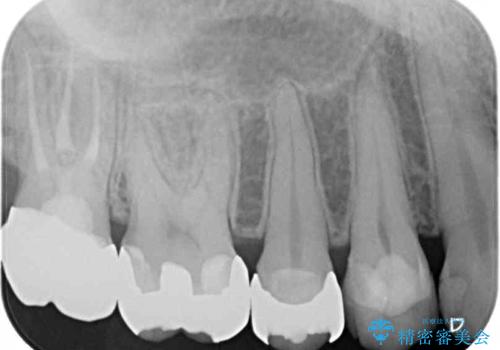

- 右上下の奥歯がむし歯でしみたり痛んだりするとのことで来院された患者様です。

下顎の奥歯は強い痛みを感じており、既に歯髄に不可逆的な炎症が起きていると診断されたため、根管治療の後にセラミッククラウンにて補綴治療を行うこととしました。

上顎の奥歯は最近銀歯による治療を行ったとのことでしたが、適合が不十分であり隙間からしみていたため、適合の良いゴールドインレーにて修復治療を行うこととしました。

下顎のむし歯は歯肉の中にまで及んでいたため、一部歯槽骨を削除し、歯肉縁上に健全歯質が位置するよう外科処置を併用しました。